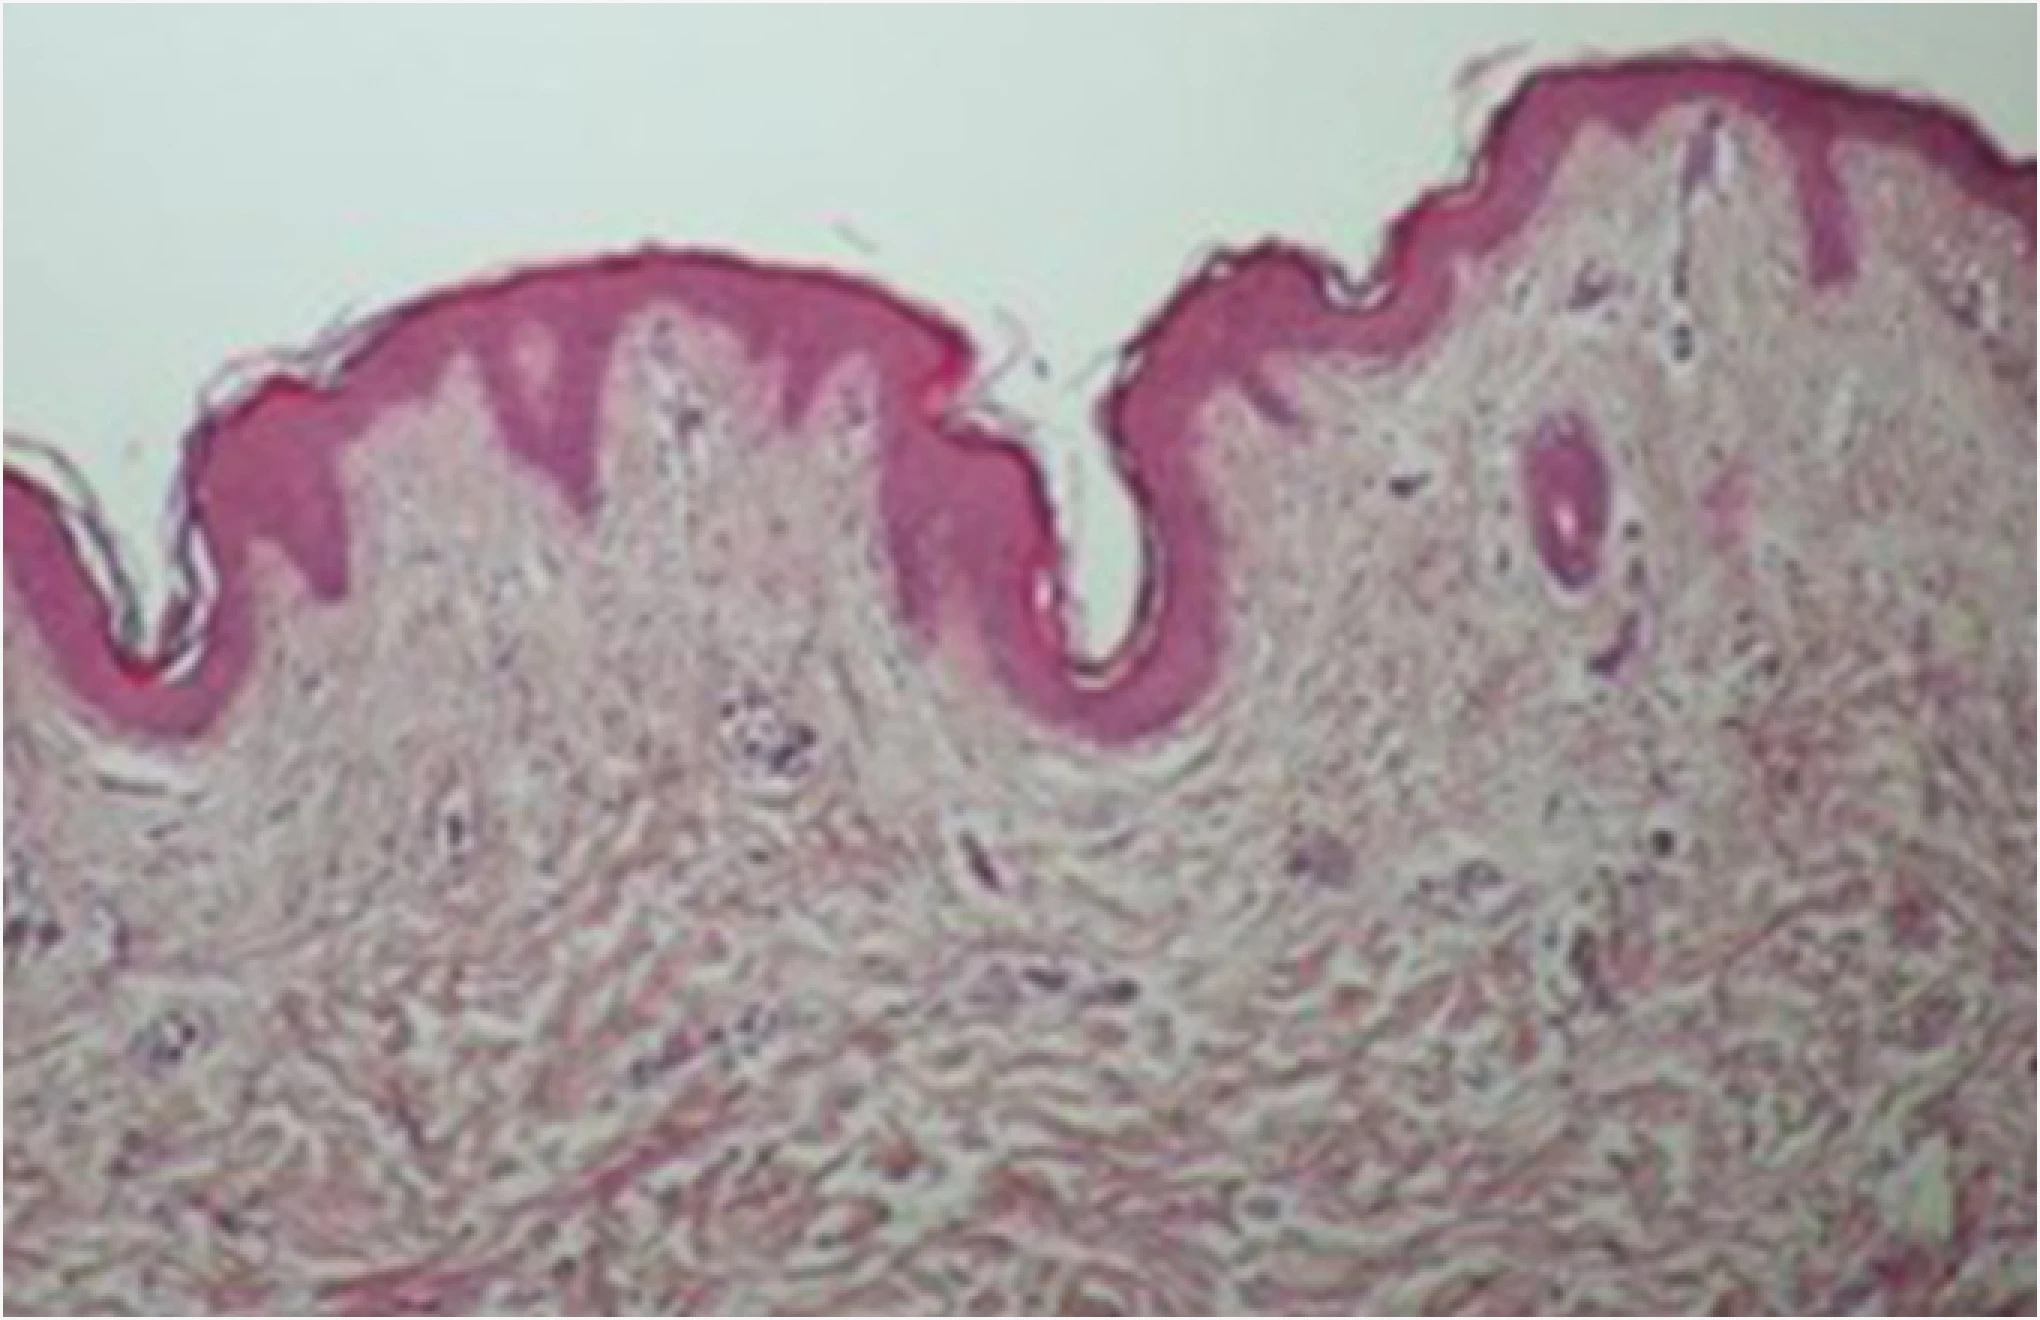

눈으로 직접 확인하는 ONDA 리프팅

콜라겐 활성의 변화

ONDA 시술 후 진피의 콜라겐이 활성화 되었음을 알 수 있고,

ONDA의 에너지가 열로 변환되면서 늘어져 있던 콜라겐을 수축시키고

리모델링을 통해 스킨 타이트닝과 리프팅 효과가 동시에 있음을 확인할 수 있습니다.

시술 전

시술 후